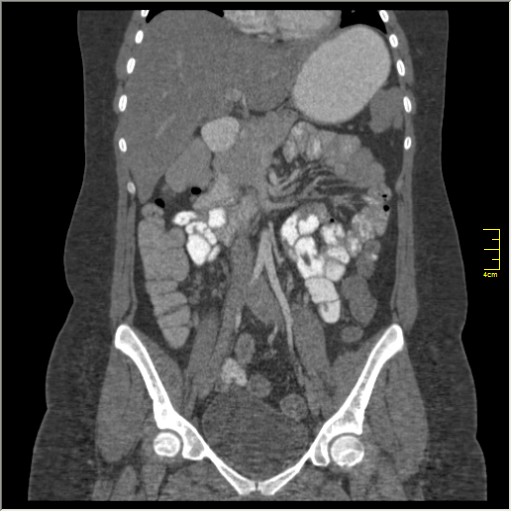

КТ энтерография

Демонстрационные изображение, оцените возможности метода! Толщина среза реконструкции 0.5-1 мм.